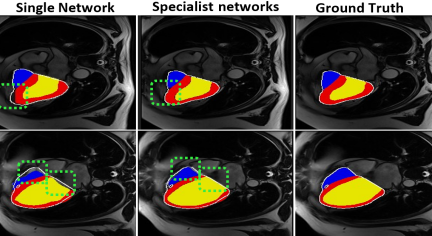

In another ablation study, we implemented the second-stage network without the specialist networks, presenting it as a single network without the inclusion of cross-E2A. The results are outlined in Table 2. While this strategy remains effective in refining the first stage predictions, there are instances where it might fail to precisely perform segmentation near the boundaries, illustrated in Fig. 4.

| Single network | 94.44 | 92.04 | 84.58 | 3.10 | 4.41 | 2.86 |

| Specialist networks (CroCNet) | 95.01 | 92.14 | 85.53 | 3.03 | 4.10 | 2.93 |